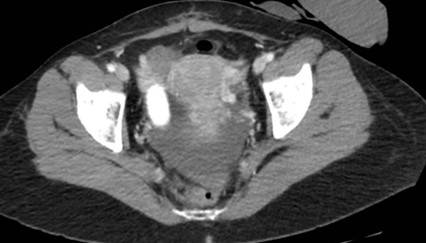

Tomografía de abdomen y pelvis con cte ev: del 13/10/2023.

Complicaciones posquirúrgicas

Tomografía de abdomen con cte ev: del 20/10/2023.

Tomografía de abdomen con cte ev: del 26/10/2023.